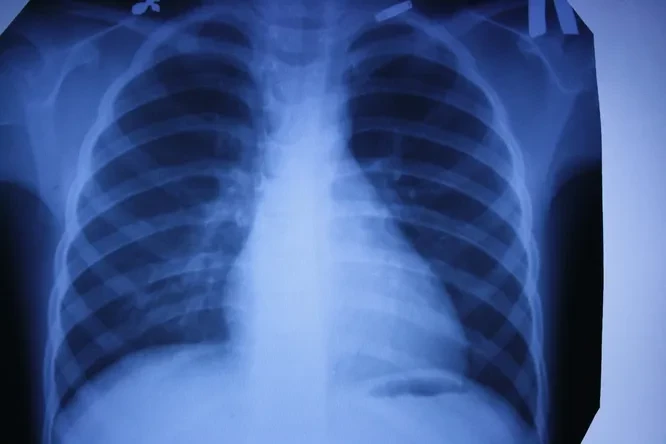

1. Рентген

Рентгеновские снимки — первая в мире диагностическая визуализация. Сложно представить современную больницу без такого обследования. Это и флюорография для проверки наших легких, и снимки при заболеваниях суставов или переломах костей. Обнаружение на ранних стадиях туберкулеза или опухоли в легких увеличивает шансы на выздоровление. Кроме того, жесткое рентгеновское излучение может уничтожать раковые клетки. Принципы современной рентгеноскопии используются и в системах безопасности (сканеры в аэропортах, вокзалах и т. д.), и в производстве. В металлургии или машиностроении равномерность просканированной X-лучами структуры указывает на хорошие прочностные характеристики деталей. Таким же образом проверяются прочность бетонных конструкций для монолитного домостроения, сварные швы сложных металлоконструкций.

Продолжая изучать X-лучи, Рентген получил на своем оборудовании первый снимок костного скелета — кисти руки. С тех пор основные элементы обычного рентгеновского аппарата мало изменились: катодная (рентгеновская) трубка, питающее устройство (два трансформатора) и пленка-фотобумага из соединений серебра с галогенами, которые темнеют с различной интенсивностью в зависимости от плотности просвечиваемого материала и тем самым формируют изображение.

В 1917 году для анализа рентгеновских снимков был применен экспоненциальный закон ослабления излучения в веществах, который показал высокую точность. Это привело к появлению компьютерной томографии (трехмерного рентгена) — послойного исследования тканей и создания изображения с учетом разности поглощения рентгеновского излучения различными по плотности тканями. Изобретатели томографа — американец Аллан Кормак, разработавший в 1963 году математический алгоритм для томографического восстановления изображения, и британец Годфри Хаунсфилдом из фирмы EMI Ltd. Британец, используя алгоритм Кормака, в 1971 году создал первый компьютерный рентгеновский томограф EMI-scanner для сканирования мозга. В 1979 году оба получили Нобелевскую премию за разработку компьютерной томографии. Томограф проводит более точное диагностирование отдельных органов, а в особенности важен для определения заболеваний мозга и сосудов. Многие жизни были спасены благодаря безошибочному определению типа инсульта при помощи компьютерной томографии, которая и до сих пор считается важным условием диагностирования такого заболевания.